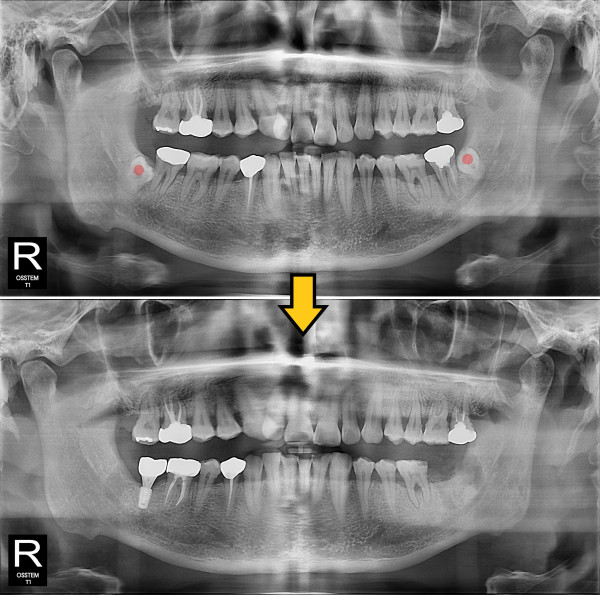

사랑니발치 30대/남성

ae27575af29d49719312fde5a1f0cca6_1764401898_7411.jpg

5e20e086184bc11a2d853605b7813944_1764319927_6616.jpg

5e20e086184bc11a2d853605b7813944_1764319927_9305.jpg